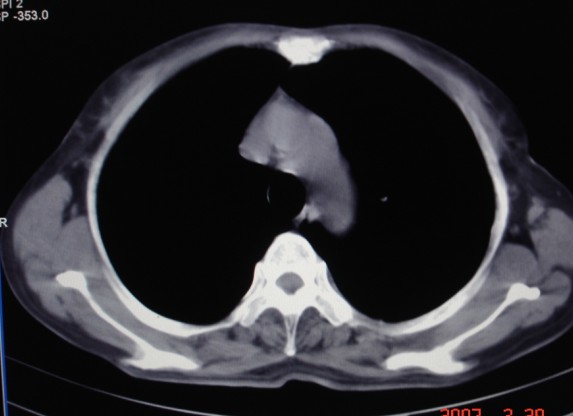

女,60岁咳嗽咳痰7天,痰中带血,有发热史,血象大约6000

双肺多发病灶,呈多形性,多叶分布,左上叶尖后段靠胸壁病灶伴有空洞,边缘模糊,与胸壁呈刀切征.

考虑混合感染以tb为主.

胸膜下结节伴空洞,结核!

支持双肺结核,左肺空洞形成。